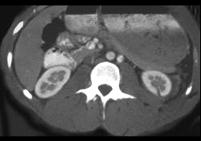

男,38岁,有外伤史,请根据所示图像,选择最可能诊断 ( )A、肾碎裂B、双肾未见异常C、肾挫伤D、微小的肾裂伤E、肾皮质缺损

问题 男,38岁,有外伤史,请根据所示图像,选择最可能诊断 ( )

选项 A、肾碎裂 B、双肾未见异常 C、肾挫伤 D、微小的肾裂伤 E、肾皮质缺损

答案 D